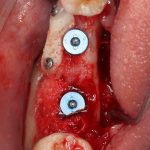

Устанавливаем формирователи десневой манжеты. Сегодня я называю эту процедуру не менее важной, чем любой другой этап имплантологического лечения:

И швы. Просто швы. Никаких дополнительных процедур.

Если честно, то сейчас бы я использовал другой шовный материал и другой тип швов. Одно неизменно, — и я об этом много раз говорил, — самая широкая часть формирователя десны должна находиться на уровне десны. Так, чтобы эффективно отрабатывать т. н. «биологическую ширину».

Через неделю я снял швы, а мой коллега Андрей Карнеев (дело было еще в НИЦ) приступил к изготовлению протезов. На это ушло полторы недели: